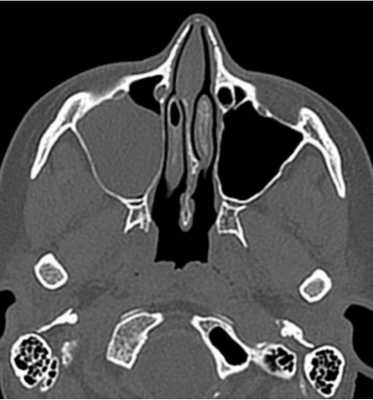

Пиоцеле (скопление гноя) задних клеток решетчатой кости